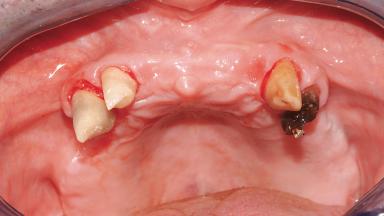

A 61-year-old male patient with a failing fixed maxillary rehabilitation and a fixed mandibular rehabilitation requested a new fixed maxillary rehabilitation. The patient was wearing a temporary metal-reinforced maxillary bridge inserted two years before the consultation. He reported that his previous dentist did not want to insert a definitive framework because he considered the residual teeth to have a negative prognosis. The patient reported a history of recurrent caries and endodontic complications as the main reason for the previous extractions. The anamnesis was negative for periodontal disease and bruxism. The patient’s chief compliant was the mobility of his maxillary prosthesis, which needed to be re-cemented frequently, and discomfort during chewing.Moreover, the patient was not satisfied with the esthetic appearance of his maxillary teeth, which he found too long. The patient asked for a stable and comfortable fixed maxillary rehabilitation and firmly rejected any removable solution.

Bone Volume Horizontally and vertically sufficient Horizontally deficient Deficient vertically or deficient vertically AND horizontally

Bone Volume Deficient horizontally, allowing simultaneous augumentation